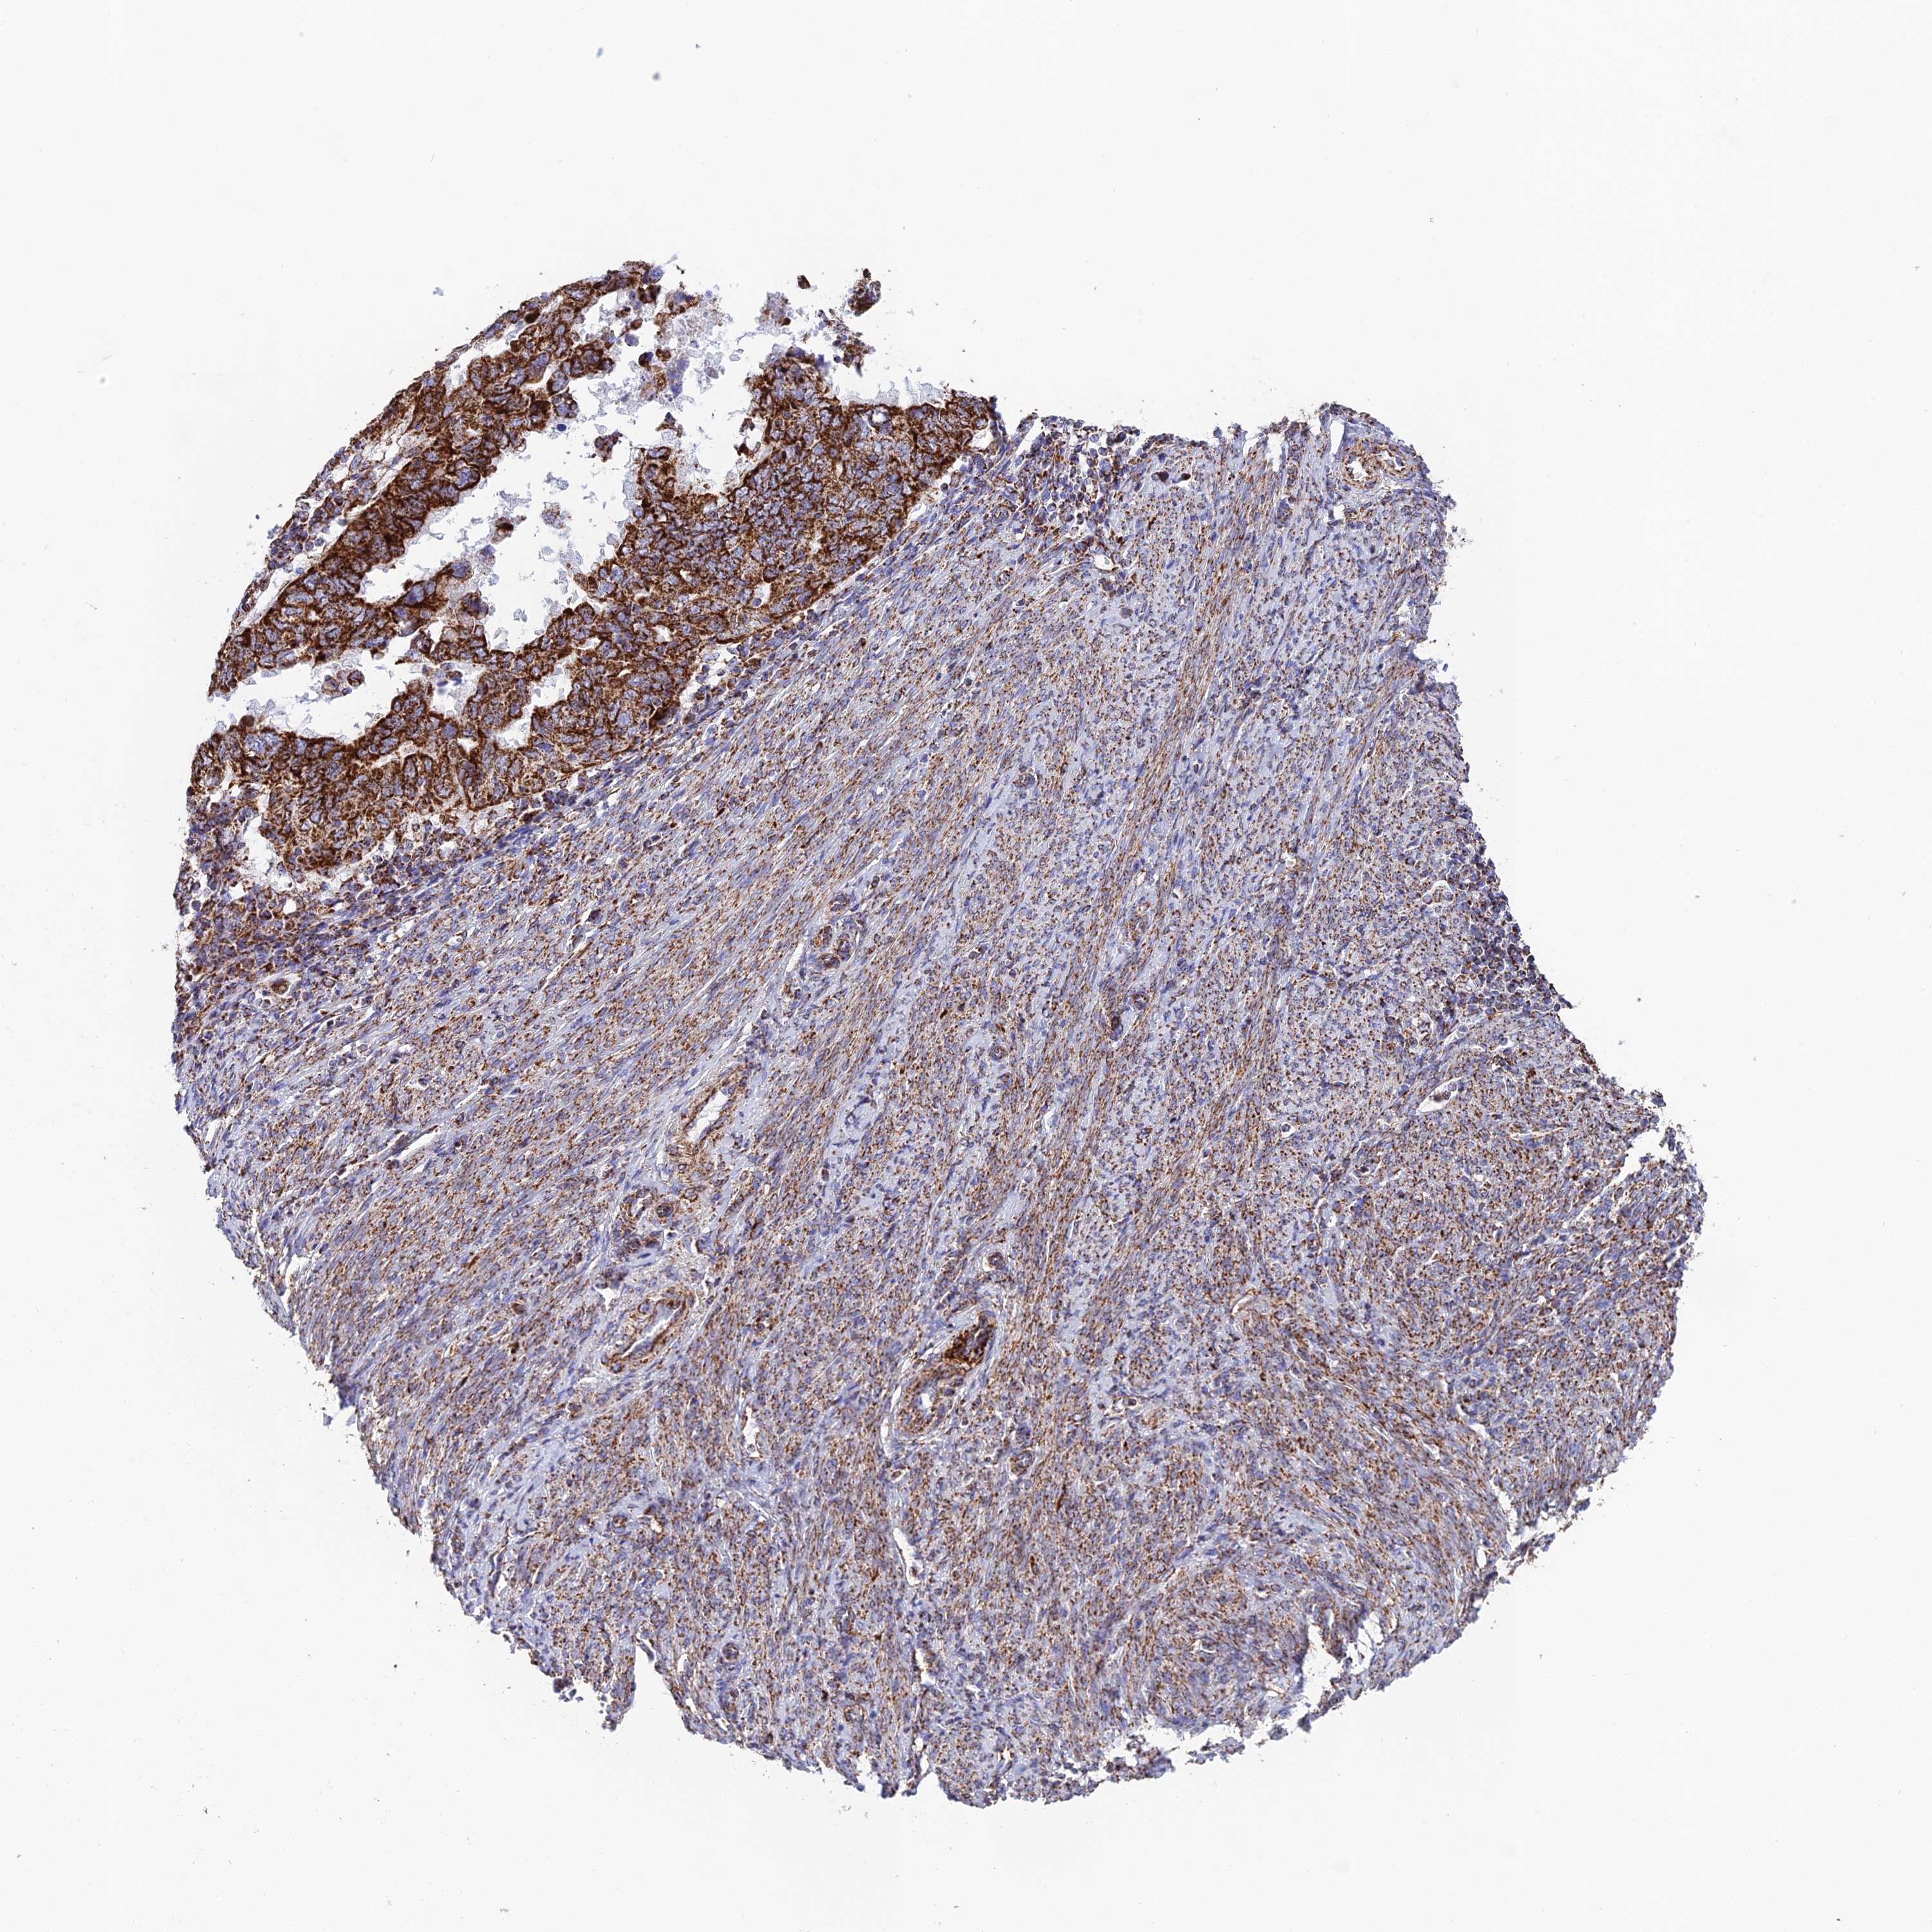

ENDOMETRIAL CANCER - Protein expressioni

A mouse-over function shows sample information and annotation data. Click on an image to view it in a full screen mode. Samples can be filtered based on level of antibody staining by selecting one or several of the following categories: high, medium, low and not detected. The assay and annotation is described here.

Note that samples used for immunohistochemistry by the Human Protein Atlas do not correspond to samples in the TCGA dataset.

Antibody stainingi

Antibody staining in the annotated cell types in the current human tissue is reported as not detected, low, medium, or high, based on conventional immunohistochemistry profiling in selected tissues. This score is based on the combination of the staining intensity and fraction of stained cells.

Each image is clickable and will lead to virtual microscopy that enables deeper exploration of all samples and also displays staining intensity scores, fraction scores and subcellular localization as well as patient and tissue information for each sample.

Antibody HPA042935

Staining

High

Medium

Low

Not detected

Intensity

Strong

Moderate

Weak

Negative

Quantity

>75%

75%-25%

<25%

None

Location

Nuclear

Cytoplasmic/membranous

Cytoplasmic/membranous,nuclear

Adenocarcinoma, NOS

Adenocarcinoma, metastatic, NOS